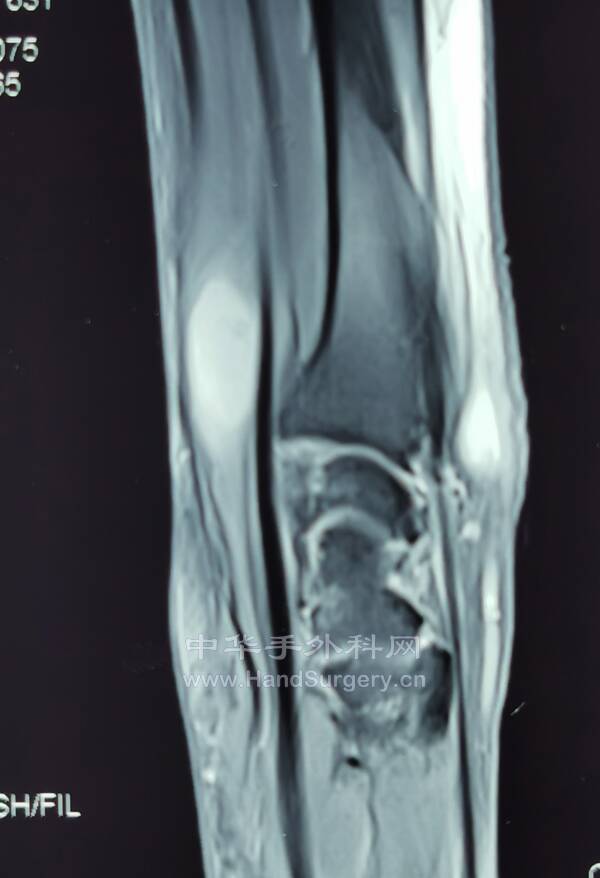

腱鞘巨细胞瘤(黄色素瘤)

沿郎格氏线设计切口